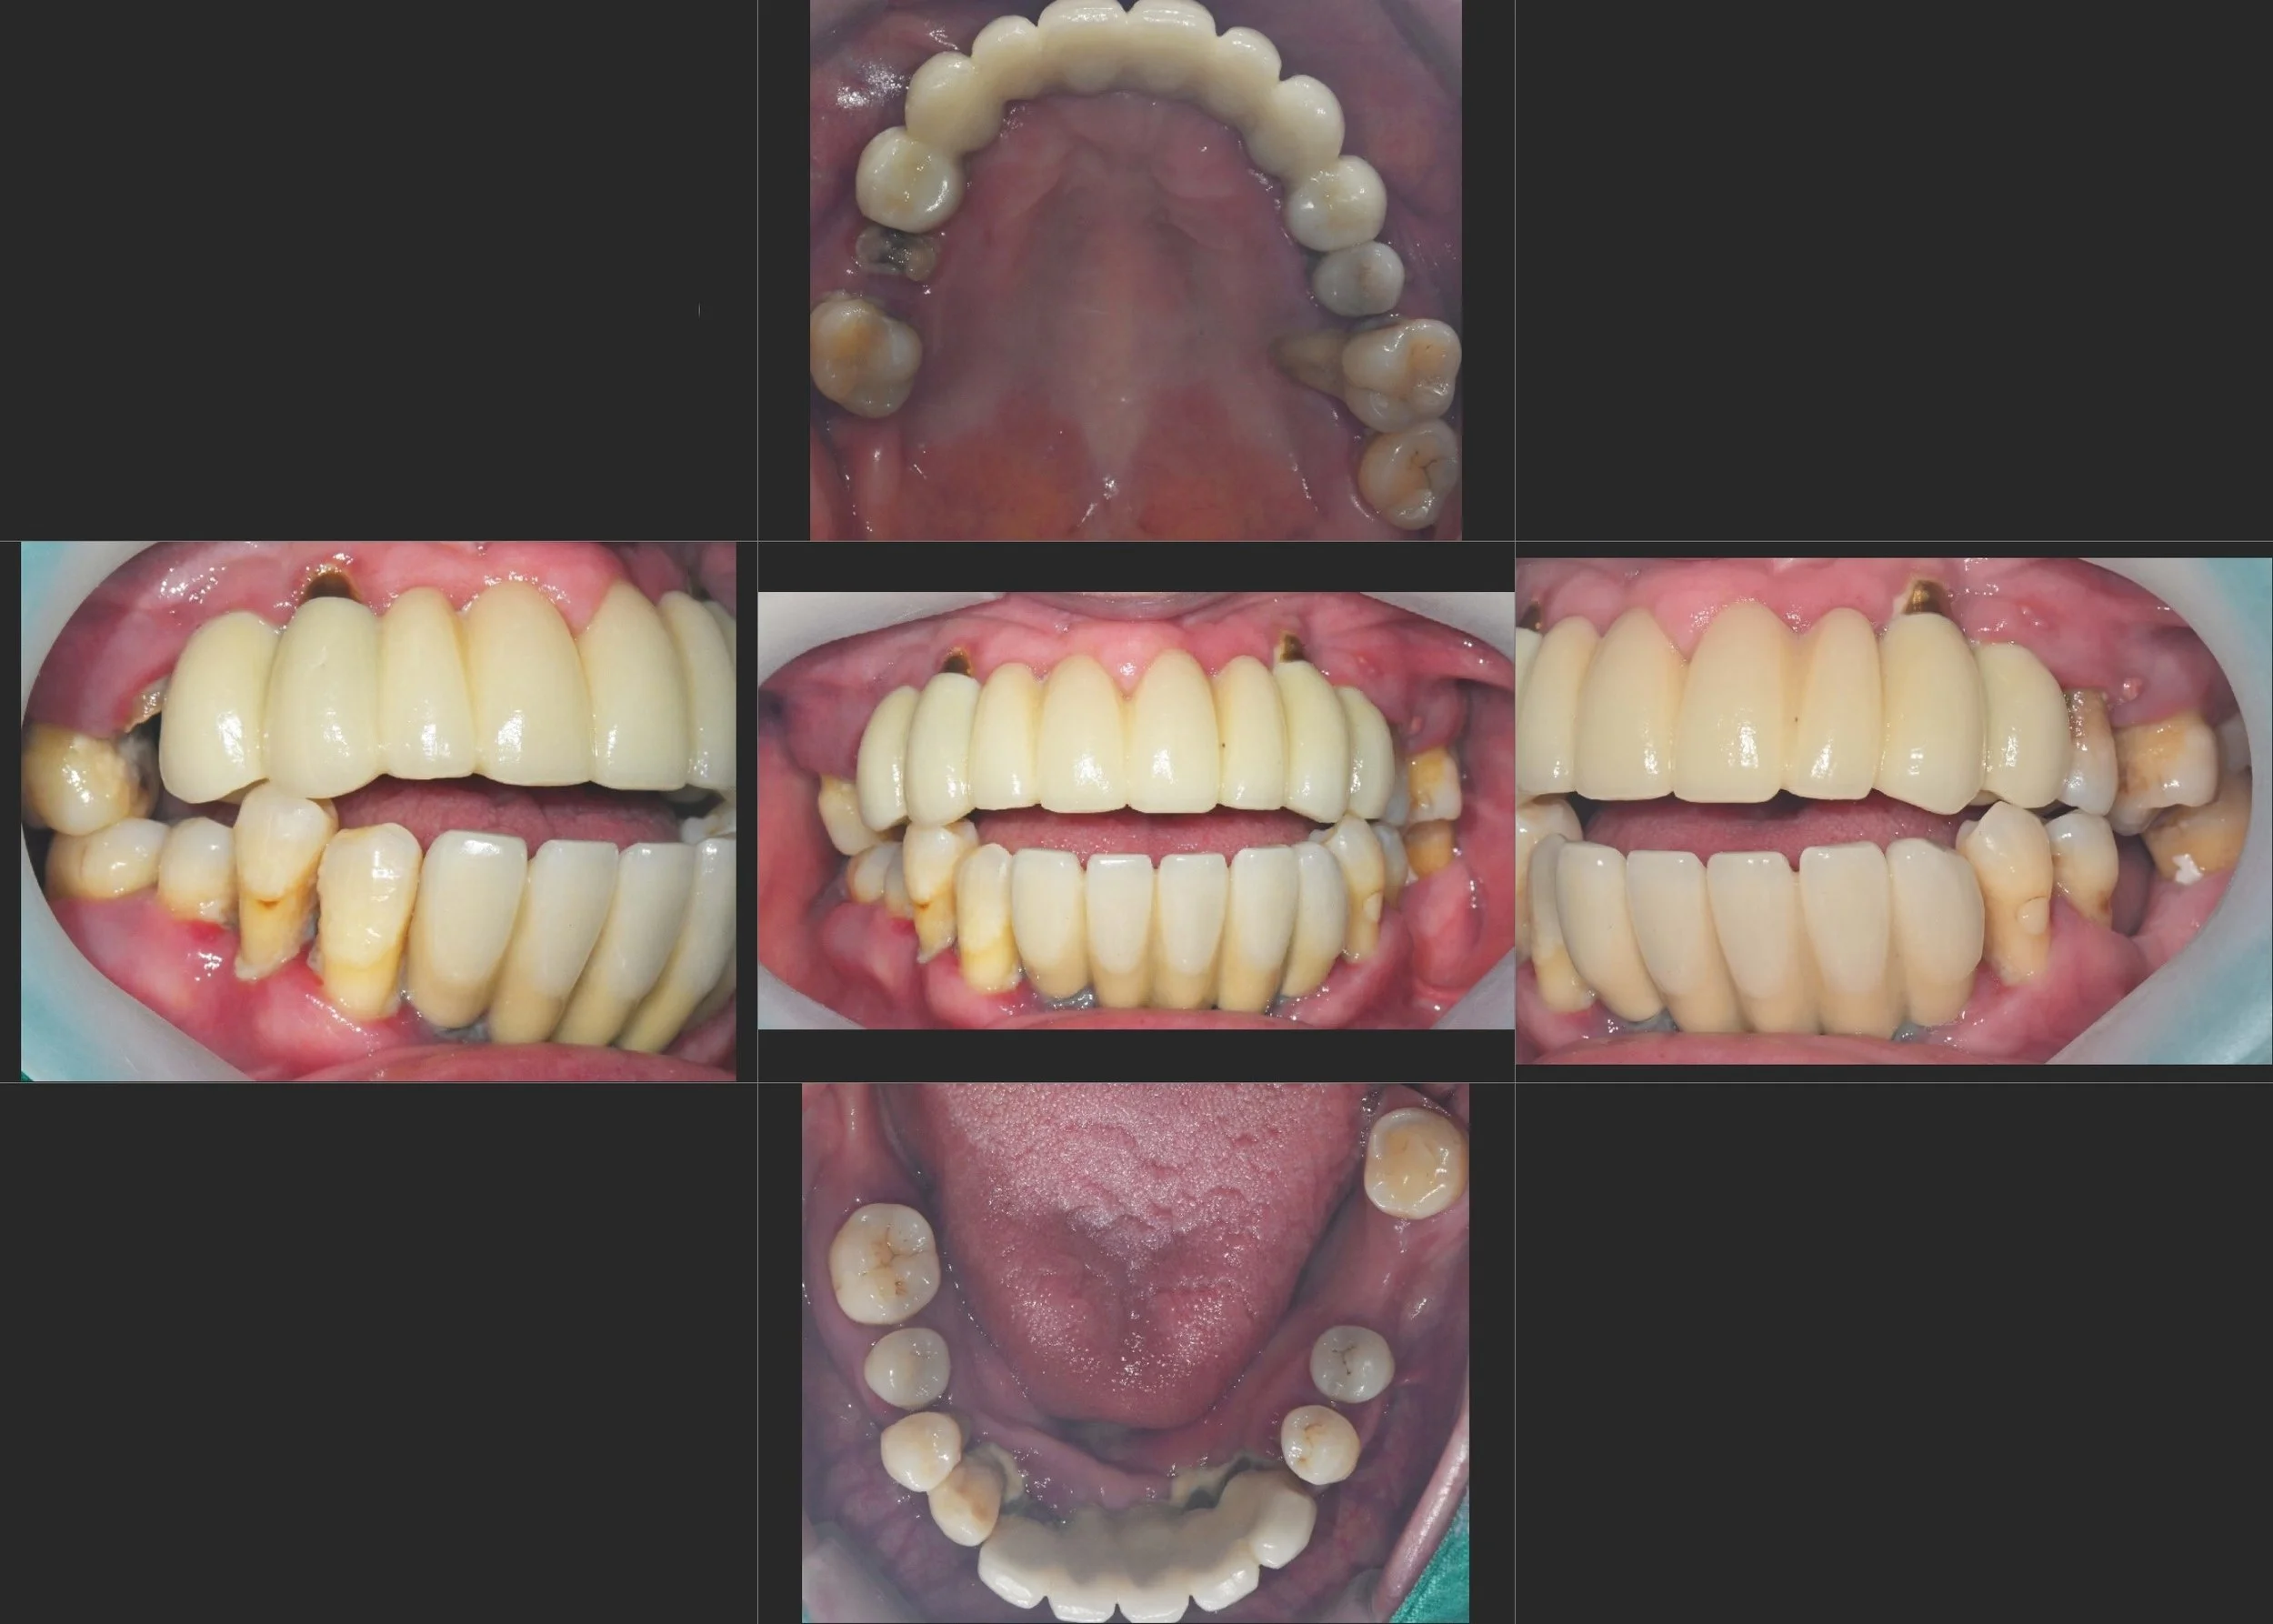

INTRA ORAL - BEFORE